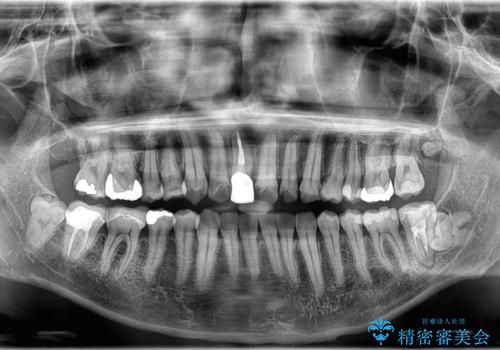

- 「八重歯と歯のでこぼこを治したい」を主訴に来院された患者様です。

歯は抜かずに奥歯の遠心移動とIPRで八重歯とでこぼこを改善しました。

左上3番は保険治療(CR)の劣化による二次カリエスになっていますので、後日治療予定です。